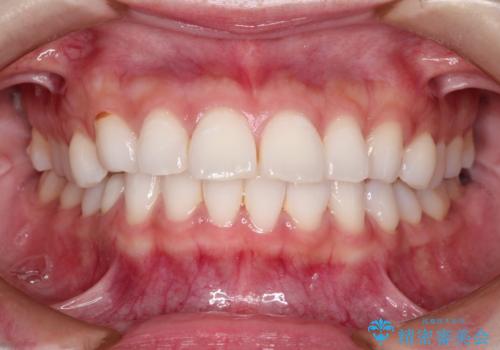

口が閉じにくい 口ゴボの抜歯矯正による改善

- 口が閉じずらく、口元が出ていることを主訴に来院されました。

上下左右の歯を1本ずつ抜歯して、そのスペースを利用して口元を引っ込める計画としました。